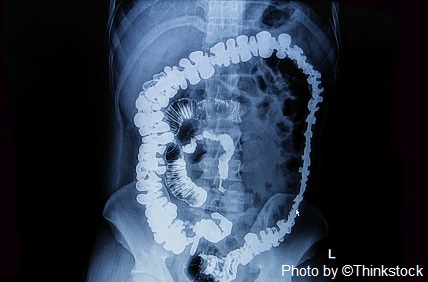

Gastrointestinal Disorders

Compared with day workers, shift workers more frequently report gastrointestinal (GI) symptoms: abdominal pain, gas, diarrhea, constipation, nausea, vomiting, change in appetite (either increased or decreased), indigestion, and heartburn.59,60 If you note onset of those symptoms, seek medical attention to treat and relieve them. Several GI disorders, such as ulcers, have higher incidence rates among shift workers.59,60 One study showed an association between shift work and colon cancer.61